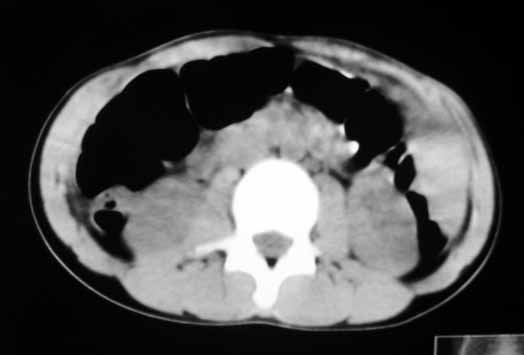

以下是引用zhangzhongshou在2007-5-22 21:04:00的发言:[br]1、脾肿大[br]2、脾脏低密度影,血管瘤?脾梗塞不能除外,建议增强扫描。

以下是引用dyqct在2007-5-22 20:45:00的发言:[br]巨脾,可疑梗塞,建议增强、查血象进一步检查

以下是引用liuyue在2007-5-23 7:57:00的发言:[br]腹主动脉周多个肿大淋巴结,脾大伴三角形低密度影,肠腔积气,考虑:1淋巴瘤2脾大伴梗塞3肠腔积气(肿大淋巴结压迫所致)